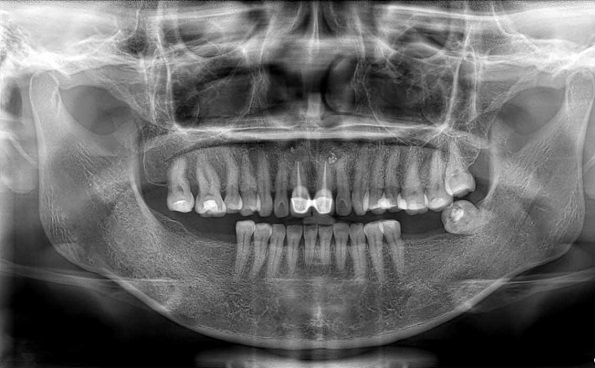

Để biết trường hợp nào có thể thực hiện trồng răng, bác sĩ sẽ cần thăm khám cụ thể, thu thập thông tin về sức khỏe của bệnh nhân và khám tổng quát khoang miệng. Quan trọng nhất chính là bước chụp Xquang để đánh giá về chất lượng – khối lượng xương hàm mới có thể đưa ra phác đồ điều trị chính xác nhất.